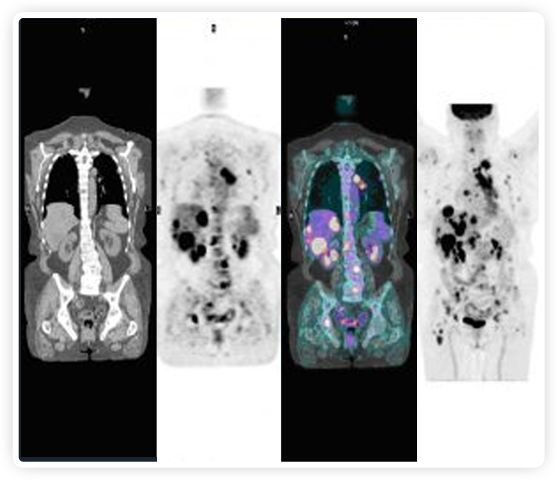

提起放療設備的引導系統(tǒng),大家通常會想到結(jié)構(gòu)性成像的CT或核磁。但你有沒有想過用功能性成像來引導放療呢?美國的一家醫(yī)療器械公司從2011年就致力于研究開發(fā)用PET提供生物學指導放射治療的設備BgRT。BgRT能實時利用癌癥的生物學特征作為信號指導治療全身腫瘤。

正電子發(fā)射斷層掃描(PET)是癌癥檢測中已建立的成像標準,與其他成像方式相比,PET能提供高靈敏度和特異性的圖像。

到目前為止,放射腫瘤學中(使用的圖像主要是結(jié)構(gòu)性的,而PET圖像可以提供生物學信息。通過使用注射示蹤劑,例如18-FDG,PET可以描繪腫瘤的代謝活性,使其“點亮”。(FDG是用于可視化癌癥代謝的最廣泛使用的示蹤劑。與正常組織相比,腫瘤細胞保留更高水平的FDG。)不同的PET示蹤劑可以識別腫瘤的不同生物學特征,例如特定生物標志物抗原(例如,PSMA)或甚至探測免疫系統(tǒng)本身(例如,PDL1表達或活化的T細胞)。

RefleXion將PET成像與立體定向放射治療相結(jié)合。在注射示蹤劑后,RefleXion的技術(shù)基于示蹤劑信號實時地在一個或多個目標上引導治療性X射線。使用這種專有方法,RefleXion的平臺有可能比現(xiàn)有系統(tǒng)向癌癥病變提供更高劑量的輻射,并改善周圍健康組織的保護。